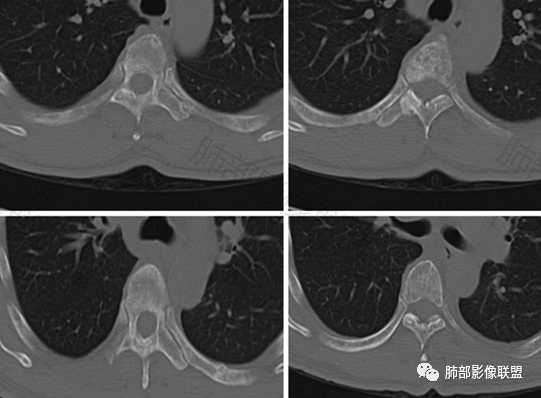

5.胸椎及肋骨见虫噬样吸收破坏,骨皮质不完整,未见硬化,骨旁软组织影增宽,未见死骨。

1.胸腺所在地不规则块影,有多结节堆积融合感,淋巴结肿大,胸椎骨及肋骨破坏,恶性肿瘤判断当无异议。

多结节堆积融合感,内乳淋巴结等肿大,似乎提示我们更像是淋巴瘤,淋巴瘤界外浸润骨骼并不少见。

3.黄勇老师曾发现胸腺类癌易转移至胸椎,本例病理报告恰恰为胸腺类癌。

这一关联性值得我们进一步总结和探讨。